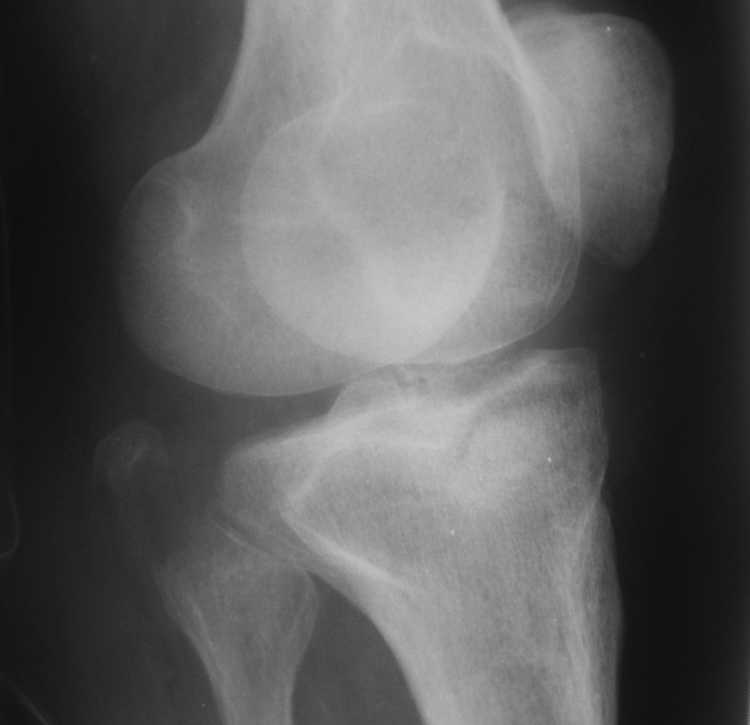

[Ortho] Помогите определиться - перелом мыщелков правой большеберцовой кости

Высылаю рентгенограммы